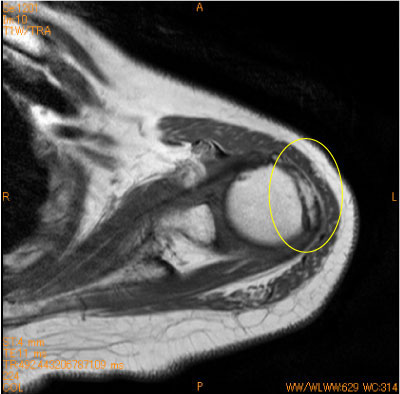

60代女性、登山で滑落。

大結節の剥離骨折は知られていないが、形態と骨挫傷が少ないことから剥離骨折が疑われる。

![]() Obl. Sag T1WI |